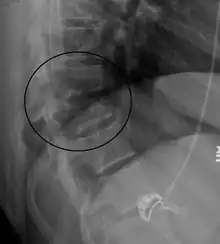

| A Chance fracture of T10 and fracture of T9 due to a lapbelt during an MVC. | |

On plain X-ray a Chance fracture may be suspected if two spinous processes are excessively far apart.[8]